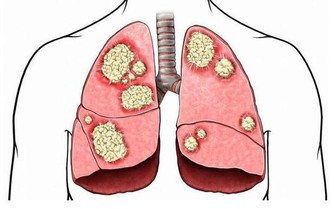

今年6月份, 這個男孩在與家裡失聯三四個月後, 他突然躺在了家門口的大街上, 手、腳腫脹, 不省人事。 送到當地醫院後, 醫生檢查後發現, 他的肺「全爛了」, 被診斷為嚴重肺結核, 病灶已經吞噬了他大部分的肺。 自從戀上網咖後, 蘇煜(化名)便走向了不歸路。 「都是作孽呀, 現在花了快10萬了(約50萬台幣),

還沒治好。 」昨天, 在河南省胸科醫院病房內, 蘇煜的父親向記者說, 目前, 他一方面奢望能有愛心人士幫幫他, 另一方面也是想以兒子的慘痛經歷給那些徹夜在網咖上網的孩子提個醒:別再拿命拼了。 以網咖為家, 不到21歲的他肺部嚴重感染 昨天上午, 省胸科醫院呼吸一病區31病床上, 蘇煜正戴著氧氣管、坐在病床上, 頭抵住一個被子睡覺。 因為肺部嚴重感染, 蘇煜不能再像正常人一樣平躺休息, 這樣的姿勢能緩解疾病的痛苦。 即便如此, 他還是會常常感覺呼吸困難。 每到此, 病床一邊的母親會趕快幫他拍背。

他迅速撥打120, 將蘇煜拉到了當地一家醫院,經檢查醫生拿著拍的片子說,「這治不了,肺都爛了。」蘇先生便帶著兒子趕到了省胸科醫院。 網咖人員聚集、空間密閉,易感染結核病菌 在省胸科醫院內,醫生通過檢查確診,蘇煜患的是嚴重肺結核,大部分肺已經被結核菌侵蝕掉。同時,他還伴有胸腔積水、上消化道出血。 經過一系列治療後,蘇煜逐漸甦醒過來。面對父母,他說得最多是「後悔」。 「前一段時間,剛接診過一個病人,也是20歲左右的小夥子,因為長期泡網吧,結果感染上了結核性腦膜炎,到醫院不到兩天就死了。」省胸科醫院一位醫生說。 「集聚的人群,密閉的空間,很容易感染結核病菌。」這位醫生說,上網容易導致疲勞、自身免疫系統功能下降,再加上網咖的人員流動性大,空氣環境不好,一旦有一個傳染源,網吧裡的其他人很容易感染上。 網吧的空氣質量到底有多差?河南電視台《民生大參考》通過專用的雷射粉塵儀,實地檢測了一下當地市區部分網咖的空氣品質,結果讓人震驚!有網吧的pm2.5濃度最高的達到了2.1毫克每立方米,也就是2100微克每立方米!!

醫生提醒,肺結核病主要是通過病人咳嗽、打噴嚏或大聲說話噴出的飛沫傳播給他人,很多一開始以為是普通感冒、慢性支氣管炎等,但是如果咳嗽、咳痰症狀持續兩週以上,或者痰中帶血,就應該引起注意,盡快到醫院做檢查。 想不到長期待在網咖會有這種性命安全的危險! 請分享給身邊常待網咖的年輕人或成年人,多一個人看到,多一份提醒!!